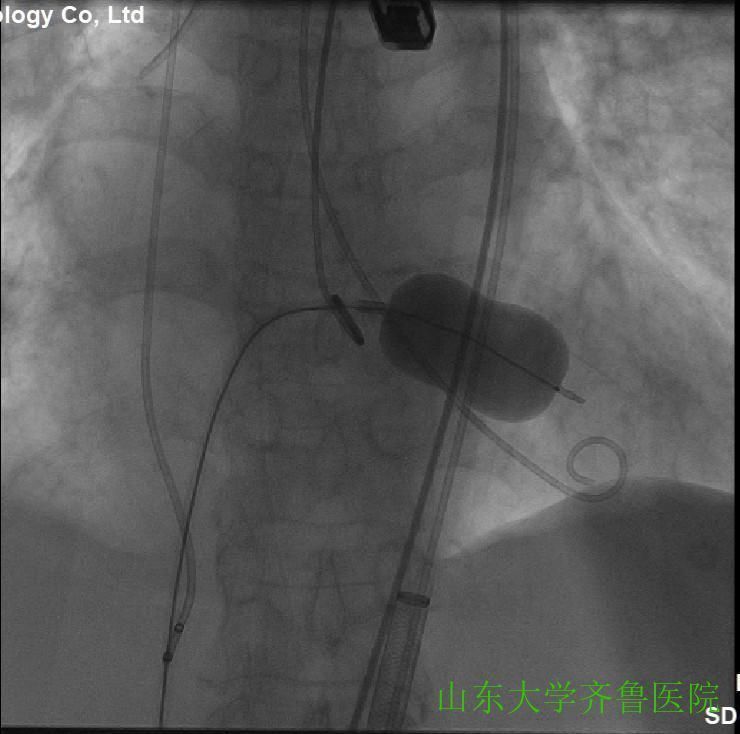

在手术室护士长翟永华及其护理团队、麻醉科吴剑波主任医师和杨绍忠主治医师的大力支持下,由心血管外科谷兴华主任医师、急诊心内科李传保主任医师、心内科安贵鹏副主任医师、心血管外科孙厚荣副主任医师及刘凯副主任医师、心脏超声室刘艳副主任医师和曹媛主治医师、放射科邵汉宏技师等在医院复合(Hybrid)手术室行一站式经导管主动脉瓣置换术(TAVR)+经皮二尖瓣球囊扩张成形术(PBMV)。手术先常规经颈静脉于右心室放置临时起搏导线并放置经食道TEE探头,行主动脉根部造影,明确主动脉瓣环平面、主动脉瓣钙化及返流情况(图1),导丝跨瓣入左心室并更换猪尾导管,测主动脉瓣跨瓣压差为76mmHg。选用24mm的擎源二尖瓣扩张球囊扩张2次,二尖瓣口面积由0.78?扩大至1.43?,并且二尖瓣无返流(图2)。选用20mmNuMed球囊,临时起搏心率180次/分,扩张狭窄的主动脉瓣(图3),应用26mmVenusA主动脉瓣介入瓣膜,准确定位、释放,造影、多体位透视及术中TTE显示介入主动脉瓣膜形态满意、无瓣周分流(图4-6)。术后即刻主动脉瓣最大跨瓣压差将至2mmHg。手术顺利,手术用时1小时40分钟,术后患者安返心脏外科监护病房。

图1主动脉根部造影,可见主动脉瓣环平面、钙化灶、主动脉瓣中度返流